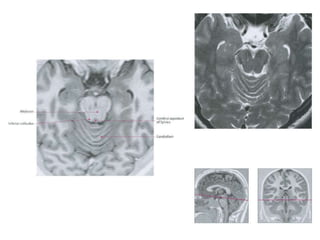

• The red nucleus and substantia nigra are

subcortical centers of the extrapyramidal motor

system.

Substantia nigra

• Pigmented layer- melanin granules

• Dorsal to peduncles and ventral to the red

nucleus .

• Composed zona compacta and zona reticulata

Red nucleus • Thered nucleus and substantia nigra are subcortical centers of the extrapyramidal motor system. • With a developed corticospinal tract, in humans red nucleus does not have a crucial role • The majority of red nucleus axons do not project to the spinal cord, but instead (via its parvocellular part) relay from the motor cortex to the cerebellum through the inferior olivary complex.

Substantia nigra • Pigmentedlayer- melanin granules • Dorsal to peduncles and ventral to the red nucleus . • Composed zona compacta and zona reticulata • The GABAergic neurons in the pars reticulata convey the final processed signals of the basal ganglia to the thalamus and superior colliculus. • The dopaminergic neurons of pars compacta mainly deals with motor control